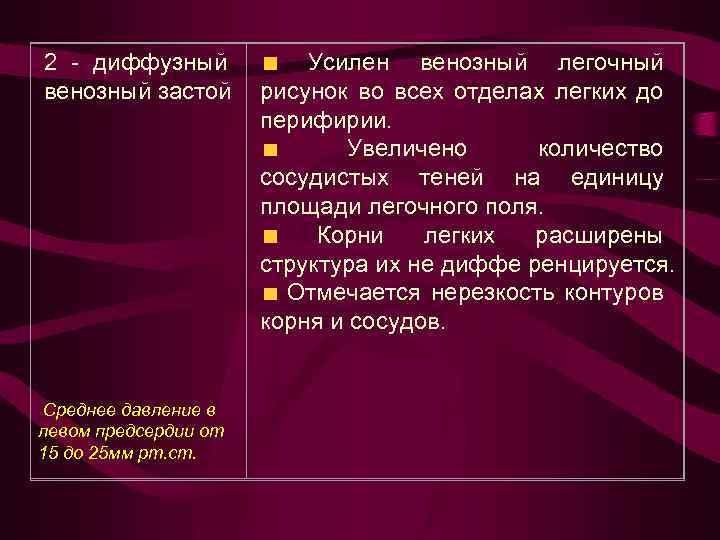

2 - диффузный венозный застой Среднее давление в левом предсердии от 15 до 25 мм рт. ст. Усилен венозный легочный рисунок во всех отделах легких до перифирии. Увеличено количество сосудистых теней на единицу площади легочного поля. Корни легких расширены структура их не диффе ренцируется. Отмечается нерезкость контуров корня и сосудов.

2 - диффузный венозный застой Среднее давление в левом предсердии от 15 до 25 мм рт. ст. Усилен венозный легочный рисунок во всех отделах легких до перифирии. Увеличено количество сосудистых теней на единицу площади легочного поля. Корни легких расширены структура их не диффе ренцируется. Отмечается нерезкость контуров корня и сосудов.